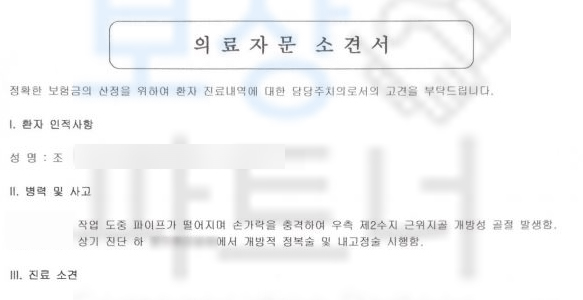

조@@님은 공사 현장에서 자재가 손가락 위로 떨어져 검지손가락이 골절되는 재해를 당하셨습니다. 진단서도 함께 보실까요?

진단서 상의 NOS는 상세불명을 의미하고, 중요한 것은 우측 제2수지 근위지골 개방성 골절 위 진단으로 인해 조@@님은 금속 고정술 즉 핀 고정을 하는 수술적 치료를 받으셨어야 했습니다.